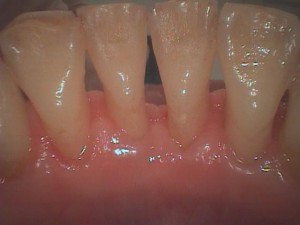

下顎の前歯です。

歯肉が下がって歯根(黄色い部分)が露出しています。

この状態が歯肉退縮です。

裏から見ても歯肉が下がっているのは明らかです。歯肉の形は歯を支える骨の形と相似形をとるので歯肉が下がっている事は骨がなくなっていると言えるのです。